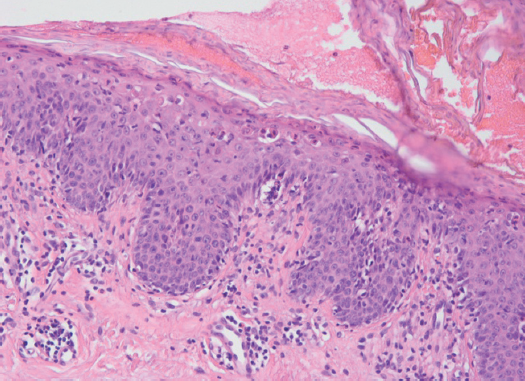

Гистологически — участок кожи покрыт многослойным плоским ороговевающим эпителием. В эпидермисе отмечается очаговый струп, паракератоз, равномерный акантоз, апоптоз клеток шиповатого слоя, вакуольная дистрофия базального слоя эпидермиса с межэпителиальными лимфоцитами. В сосочковом слое дермы наблюдается периваскулярный смешанный клеточный инфильтрат, преимущественно из лимфоцитов с примесью единичных эозинофилов (рис. 2).

Рис. 2. Тот же больной. Гистологическая картина. Диагноз: «Эритродермия». В эпидермисе отмечаются паракератоз, неравномерный акантоз, единичные апоптотические клетки в шиповатом и зернистом слоях эпидермиса. В дерме выявляется периваскулярный лимфоцитарный инфильтрат с тенденцией к проникновению в эпидермис (экзоцитоз). Окраска гематоксилином и эозином. Увеличение ×100

Fig. 2. The same patient. Histologic picture, the diagnosis – an erythroderma. In epidermis parakeratosis, irregular acanthosis, single apototic cells in suprabasal and granular layers are noted. In derma there are perivascular lymphocytic infltrates with a tenedention to penetration into epidermis (exocytosis). Colouring hematoxylin and eosin. Increase ×100

В то же время гистологические признаки эритродермии, вызванные лекарственными препаратами, соответствуют модели воспаления interface (вакуолярный тип) дерматита 1 [6, 8]:

- гидропическая (вакуольная) дистрофия базального слоя эпидермиса;

- лимфоциты в базальном слое эпидермиса;

- коллоидные тельца (апоптотические клетки) в разных слоях эпидермиса.